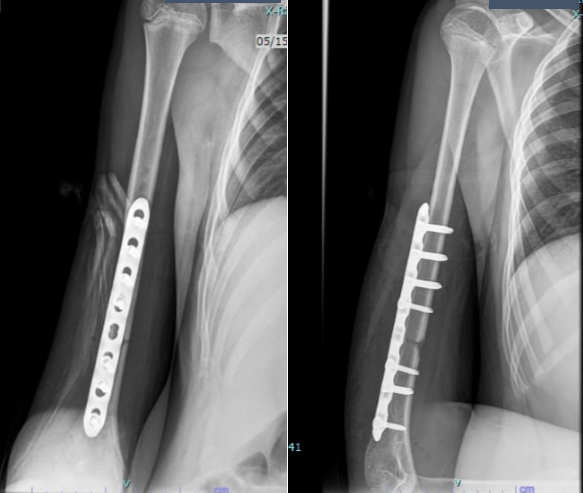

The injury was closed, with no neurovascular deficit. After discussion with the family, he underwent open reduction and internal fixation with plating. The procedure was uneventful, and he was discharged a few days later with intact neurovascular status (Fig. 2).

Figure 2: Post-operative radiograph after plating.

His wounds healed well, and there were no complications during the initial post-operative period. However, even after 7–8 months, radiographs showed no signs of union (Fig. 3 and 4).

Figure 3: Radiograph at 7 months showing non-union.

Figure 4: Radiograph at 8 months confirming non-union.